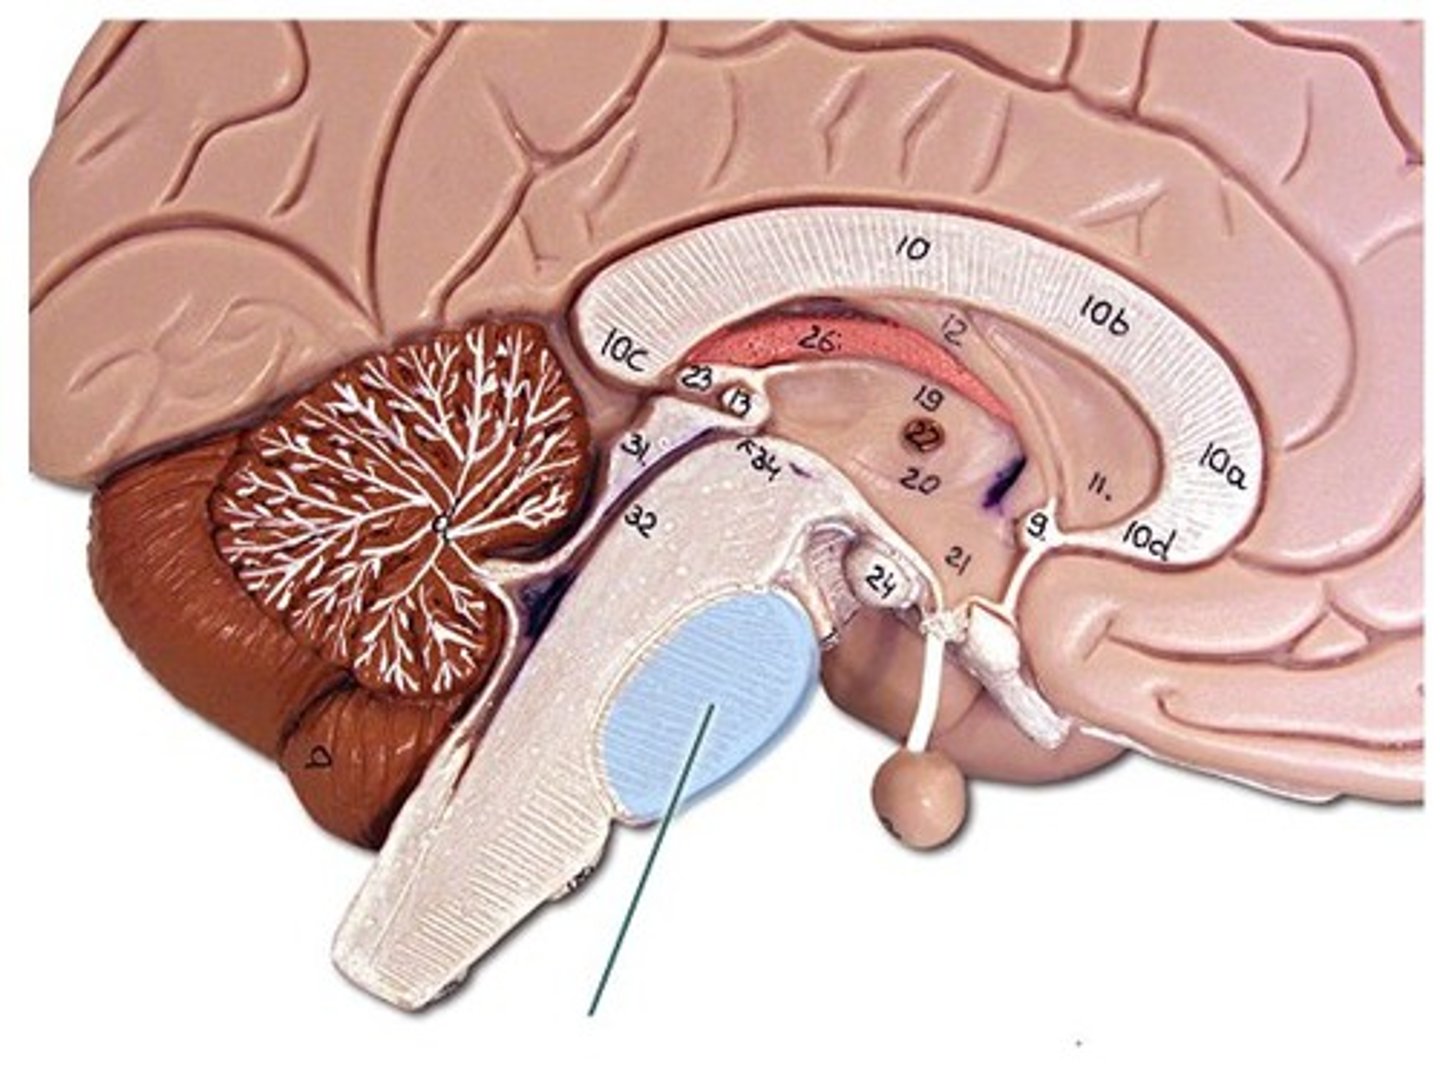

corpus collosum

part of the cerebrum. white matter. Myelinated Axons. It's job is to allow communication between the left and right hemispheres.

fornix

connects the hypothalamus and the hippocampus.

diencephalon

includes some of the area of the limbic system.

- acts as a connector in the brain.

- Connects cerebrum with the lower parts of the brain. Includes the pituitary gland, thalamus, hypothalamus, mammillary bodies, and pineal body.

pituitary gland

the thing it hangs from is the infundibulum (the stalk that it hangs from. It regulates hormones. Releases hormones that control other endocrine glands. Releases tropic hormones.

infundibulum

The stalk that the pituitary gland hangs from.

thalamus

receives and filters incoming sensory information. All the senses except for smell hit thalamus first. With generalized and specified senses.

interthalamic adhesion

in the center of the thalamus. It connects the thalamus in the right and left hemisphere of the brain.

hypothalamus

This is the big cross roads. Master control of the autonomic nervous sytem (heart rate, blood pressure, digestion, parts of urination, respiration).

- Master control of the endocrine system - secretes hormones that tell the pituitary gland what to do. Pituitary gland cannot act unless it has orders from hypothalamus.

- Makes some hormones too that it stores in pituitary gland.

- Regulation of body temperature.

- Control of emotional behavior (seat of the limbic system). Center of it.

- Helps us to integrate feelings/ have complex feelings.

- Controls food and water intake (initiates thirst mechanism) . detects blood osmolality.

- Regulation of sleep-wake (circadian rhythms).

mammillary bodies

two bumbs between pituitary gland and brain stem. Part of limbic system. Contributes to functioning of limbic system.

pineal body

considered an endocrine gland. Secretes melatonin. Plays a role in circadian rhythm - regulation of this. Sleep/wake cycles or night/day cycles. They don't know exactly how this works, but if the pineal gland does not release melatonin, you can have differences in circadian rhythm.

brain stem

Includes the mid brain, pons, and medulla oblongata.

midbrain

corpora quadrigemina,connector of cerebrum, diencephalon, and cerebellum to spinal cord. Connector in central nervous system.

corpora quadrigemina

Also known as the tectal plate. Consists of the superior colliculi and the inferior colliculi.

superior colliculi

bumby part on opposite side of pituitary gland. Top one. Responsible for visual reflex (track objects visually). If we see something in peripheray, we can turn towards object. Instinctive reflex.

inferior colliculi

bumpy part on opposite of pituitary gland. Bottom one. 31 auditory tracking. If we hear a loud noise, we can move toward it.

pons

contains parts of respiratory center. Plays a role in controlling breathing rate and depth.

medulla oblongata

has a cardiac center. Plays a role in influencing heart rate and the force of the contractions in the heart. In response to changes in blood pressure and oxygen levels.

- vasomotor center - helps to control blood pressure. Sends out signals that causes vasoconstriction or vasodilation of blood vessels. Contains parts of respiratory center.

- initiates inspiration and respiration.

cerebellum

cerebellar hemispheres, cerebellar cortex, and arbor vitae.-

the little brain.

- Function: coordinates all voluntary movements. Ability to ride a bike, dance, anything complicated that calls for coordinating movement between left and right sides with skeletal muscles.

- Ability to move joints in a coordinated fashion- cerebellum in charge.

cerebellar hemispheres

divided by vermis.

cerebellar cortex

outer covering of cerebellum - gray matter.

arbor vitae

"tree of life" white matter in cerebellum.

ventricles

cavities in the brain. Includes lateral ventricles - right and left, third ventricle, fourth ventricle, cerebral aqueduct, and choroid plexus.

lateral ventricles (left and right)

right and left. Actual open space. Behind the corpus collosum.

- Cerebrospinal fluid circulates through these ventricles and underneath the meninges.

- Gives the brain buoyancy.

- brain floats a little bit and this prevents trauma.

third ventricle

in the area where the hypothalamus is.

fourth ventricle

located beneath the arbor vitae in the cerebellum.

cerebral aqueduct

connector between third and fourth ventricle in front of colliculi.